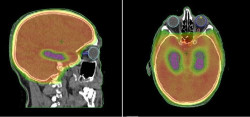

Un estudio cambia el abordaje del tratamiento de la metástasis cerebral en cáncer de pulmón

El Servicio de Oncología Radioterápica del Hospital del Mar de Barelona ha coordinado un estudio que demuestra que proteger el hipocampo de la radiación en aquellos pacientes con cáncer de pulmón de células pequeñas que tienen que someterse a radioterapia para evitar la aparición de metástasis en el cerebro es una "estrategia válida" para proteger su memoria sin afectar sus probabilidades de supervivencia.